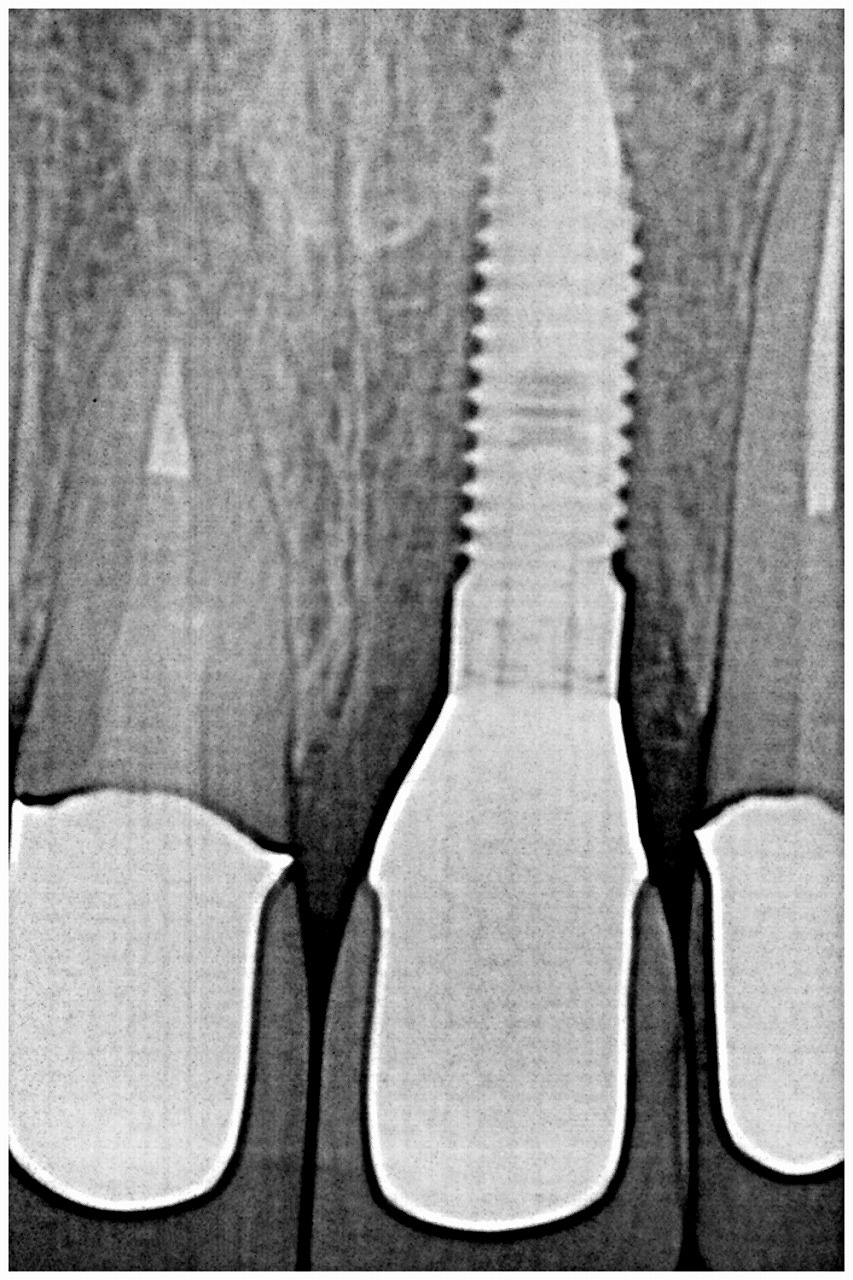

インプラント埋入時になります

インプラント埋入深さはこの程度

機能時のデンタルレントゲンになります